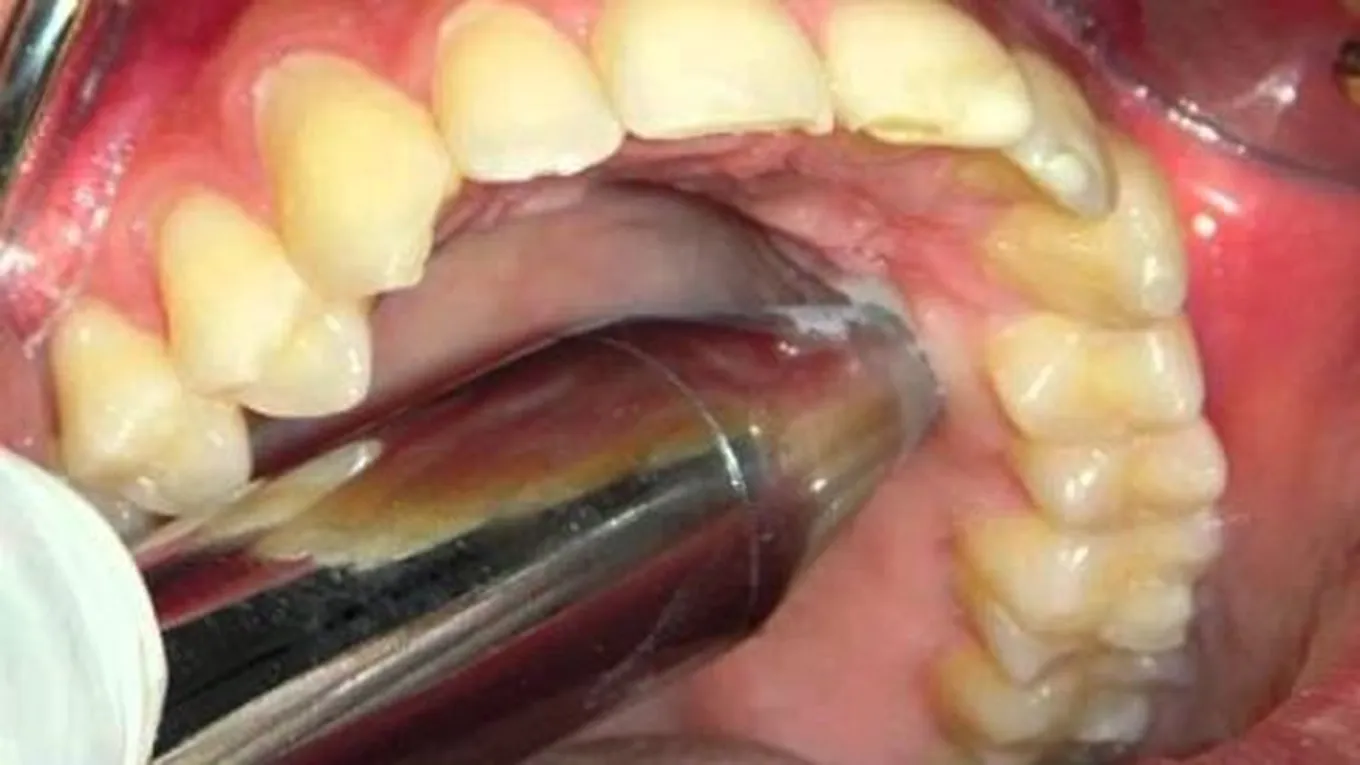

خراج الأسنان هو التهاب يصيب جذور الأسنان، بسبب البكتيريا التي تدخل إليه عبر التجاويف، ويكون على شكل انتفاخ بالقرب من الأسنان، ويرافقه ألم شديد، مع وجود قيح، وشعيرات دمويّة بارزة، وتعزى الإصابة به بشكل عام إلى إهمال نظافة الفم والأسنان، وإهمال علاجه يؤدي إلى تلف جذور الأسنان، وبالتّالي اختفاء الألم، ولكنّ ذلك لا يعني انتهاء المشكلة فالعدوى ستنتقل إلى أسنان أخرى، وتنخر في عظام الفك، ممّا يؤدي إلى تلفها وإذابتها وتجدد الألم.

يحدث خراج الأسنان بسبب البكتيريا الموجودة في الفم، وهناك عدّة عوامل تسبب ظهور خراج الأسنان، ومن أهمها:

- تسوس الأسنان الشديد، وهو التسوس الواصل إلى جذر السن بسبب إهمال نظافة الأسنان، فيبدأ التسوس من تاج السن حتى يصل إلى الجذر.

- أمراض اللثة وخاصّة التهاب اللثة الشديد.

- التعرض لحادث ما يتسبب في تكسر السن، وبالتّالي عمل تجاويف تسهّل وصول البكتيريا إلى تجاويف الجذور.